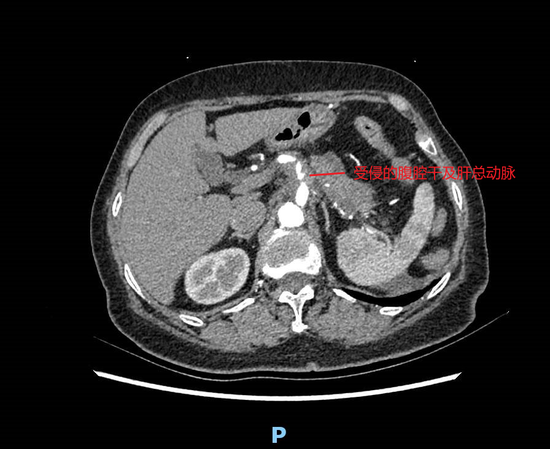

患者刘某,女,73岁。6个月前出现上腹部胀痛,伴腰背部放射痛,食欲下降,10月4日来滨医附院住院治疗,诊断为胰腺癌(体尾部)。影像学检查提示患者肿瘤浸润侵犯范围较广,自门静脉前方胰腺组织一直蔓延至胰尾部,侵犯腹腔干、肝总动脉等腹部重要大血管,并累及胰腺上、下缘腹膜后组织。同时,患者合并有心律不齐、高血压病等基础病史,使得患者治疗难度及风险均明显增高。

滨医附院肝胆外科在陈强谱教授带领下,认真讨论患者病情,反复研判患者影像资料,结合患者肿瘤浸润情况,精细设计手术方案。积极术前准备后,给予患者行联合腹腔干切除顺行模块化胰脾切除术,即胰腺癌改良Appleby术,术中发现肿瘤累及门静脉左侧壁,一并行门静脉部分切除、肠系膜下静脉补片修补术。手术历时6个小时,顺利完成。上述肿瘤联合腹腔干切除及门静脉切除重建使得手术达到了根治性切除。术后在医护团队的共同努力下,运用加速康复(ERAS)方案,患者恢复良好出院。出院前复查相关检查见患者肝脏血运良好,门静脉系统通畅无狭窄。

该术式涉及到腹部大血管的切除,面临着术后肝脏缺血的高风险,对外科医生的要求极高,需要非常熟悉胰腺区域解剖特点、血管走行与变异,并具有丰富的腹部血管切除重建的临床经验才能完成。该患者在行改良Appleby手术基础上,同时完成了门静脉的部分切除、肠系膜下静脉补片的修补术。